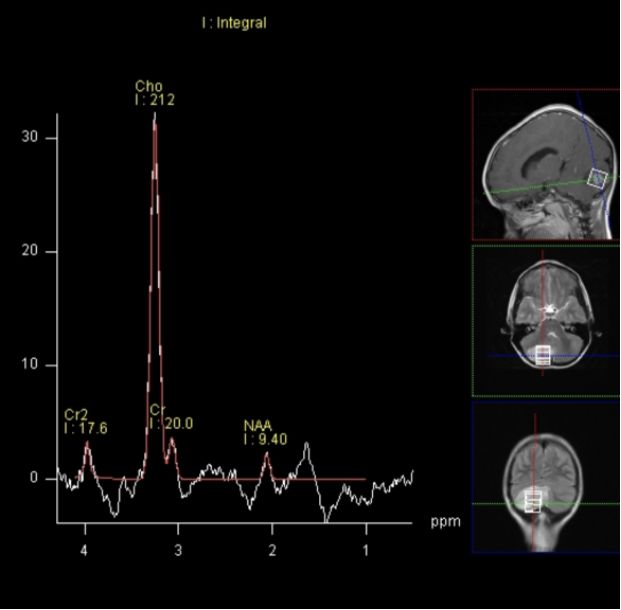

在1H-MRS上高胆碱(Cho)峰、低N-乙酰天冬氨酸(NAA)峰与肿瘤侵袭性密切相关。研究表明髓母细胞瘤在MRS会表现为Cho峰、Cho/肌酸(Cr)比值及Cho/NAA比值显著升高,NAA峰明显降低,并且髓母细胞瘤Cho峰明显高于其他后颅窝肿瘤[6](图9)。同时在MRS中选择短TE(20ms)的激励回波成像,可检测到所有髓母细胞瘤均出现了牛磺酸(Tau)峰,其共振峰位于3.3ppm,认为Tau是髓母细胞瘤特异性的生物标记物[6]。

图9. 髓母细胞瘤在MRS表现为Cho峰、Cho/肌酸(Cr)比值及Cho/NAA比值显著升高,NAA峰明显降低 [8]